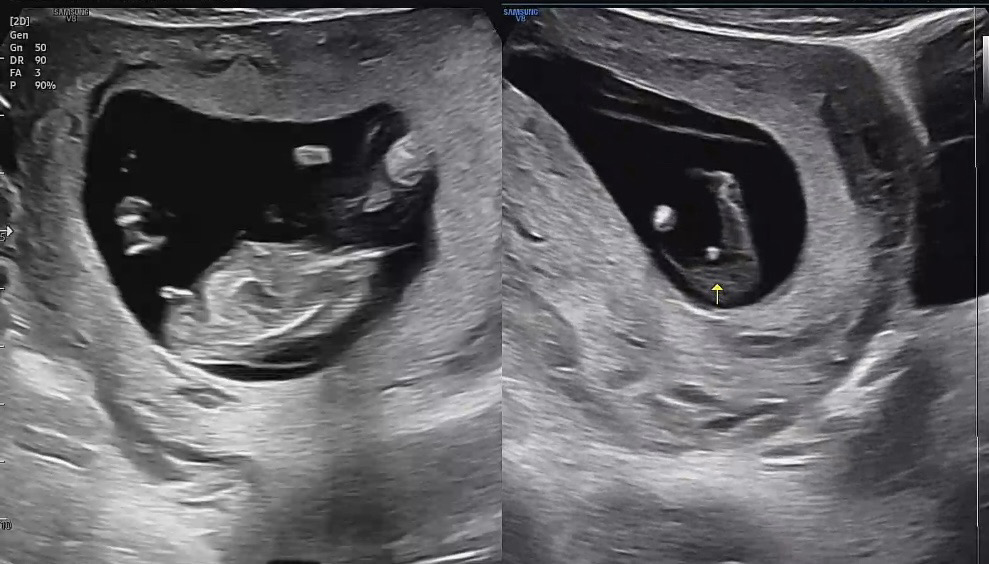

성별 추측(12주 1일)

초음파 보시면서 원장님이 🌶️ 가능성이 있어 보인다 하셨는데 진짜일까요? 아직 좀 이른 것 같지만 궁금해서 여쭤봐용..🥹 딸일까요 아들일까요? 추측 부탁드려요!😆